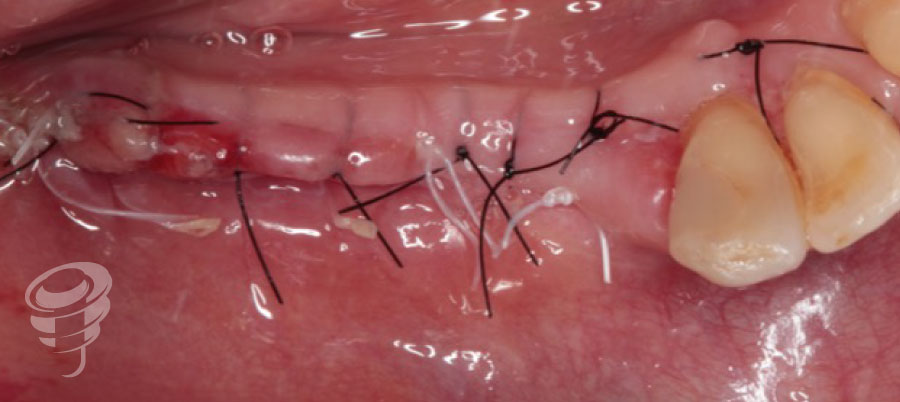

Fig 16. Puntos de sutura colchoneros horizontales de aproximación con Goretex y puntos de sutura simple con Supramid 4/0.